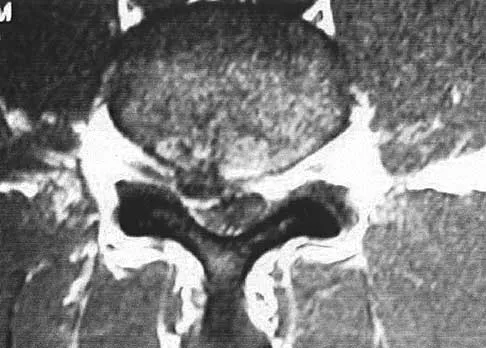

Figures 1a through 1c show the radiograph and MRI scans of a 16-year-old patient who has a painful hip. Examination reveals a significant limp, limited abduction and internal rotation, and severe pain with internal rotation and adduction. A biopsy specimen is shown in Figure 1d. What is the deposited pigment observed in this condition?

Pigmented villonodular synovitis (PVNS) is a synovial proliferative disorder that remains a diagnostic difficulty. The most common clinical features are mechanical pain and limited joint motion. On radiographs, the classic finding is often a large lesion, associated with multiple lucencies. Other findings may include a normal radiographic appearance, loss of joint space, osteonecrosis of the femoral head, or acetabular protrusion. MRI is the imaging modality of choice and will show the characteristic findings of a joint effusion, synovial proliferation, and bulging of the hip. The synovial lining has a low signal on T1- and T2-weighted images, secondary to hemosiderin deposition. Copper deposition occurs in patients with Wilson's disease, which mainly affects the liver. Bhimani MA, Wenz JF, Frassica FJ: Pigmented villonodular synovitis: Keys to early diagnosis. Clin Orthop 2001;386:197-202.